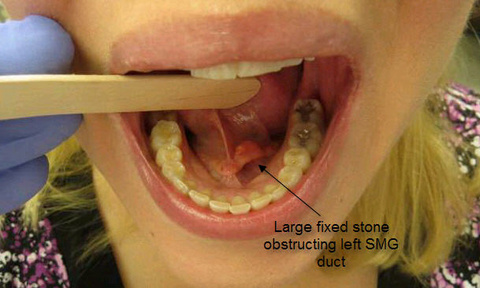

In the absence of bacterial contamination chronic obstruction to outflow of saliva from a major salivary gland often results in its involution as a non-functional asymptomatic remnant of a gland. Although the goal of sialendoscopy-assisted gland-preserving surgery in the management of salivary obstruction from stones and strictures is relief of symptoms and restoration of normal salivary flow, sometimes these dual goals are not achieved. Relief of painful swelling of salivary glands may occur without normal production of saliva when the gland atrophies or involute. Examples of cases are listed below:

44 year old with intermittent swelling of the left submandibular gland for 15 years without treatment to date: